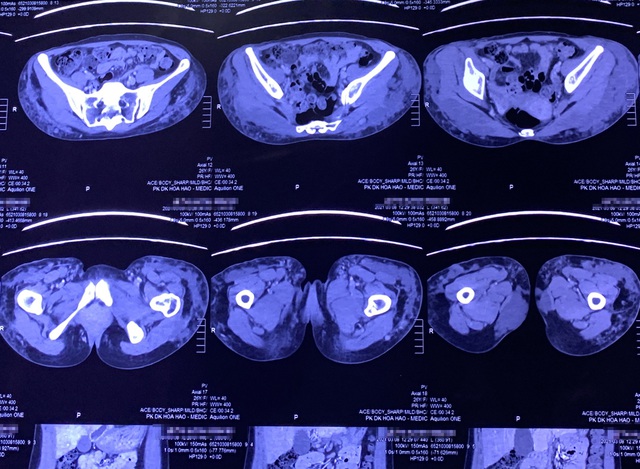

Hình ảnh kiểm tra của bác sĩ cho thấy những tổn thương nghiêm trọng ở vùng mông của người bệnh.

Bác sĩ tiến hành phẫu thuật xử lý filler đang ăn mòn cơ thể của người bệnh.

Qua thăm khám trực tiếp và chẩn đoán kết quả chụp MRI, bác sĩ Tú Dung phát hiện filler đã lan rộng khắp vùng mông trái của bệnh nhân, đến tận khu vực xương chậu, khiến cho mông bị sưng phồng, cứng ngắc, nhiều vùng bị vón cục. Nếu không điều trị khẩn cấp sẽ dẫn đến hoại tử. Ở giữa vùng biến chứng filler có vết thương sâu, liên tục chảy dịch, khiến bệnh nhân đau đớn. Ngay lập tức, bác sĩ Tú Dung chỉ định mổ khẩn nạo vét filler trong cơ thể bệnh nhân.

Khoảng 500ml filler có lẫn máu mủ được bác sĩ lấy ra từ cơ thể bệnh nhân sau phẫu thuật.

Trong quá trình phẫu thuật, khi bác sĩ vừa bóc tách và rạch đường phẫu thuật đầu tiên, filler và dịch mủ trào ra ào ạt, có màu trắng đục và nhớp dính như gel. Filler len lỏi sâu vào các mô cơ khiến vùng mông của bệnh nhân chỗ lồi, chỗ lõm, biến dạng, chỗ bị xuyên thủng, hình thành khối tổ ong bên trong mô mềm. Nguy hiểm hơn, filler thẩm thấu và lan rộng tới tận xương chậu của bệnh nhân, gây tắc nghẽn mạch máu nuôi dẫn đến hoại tử mô và nhiễm trùng nặng.

Các bác sĩ đã mất khoảng 4 giờ để thực hiện cuộc phẫu thuật loại bỏ filler cho bệnh nhân.

Theo phân tích của BS Tú Dung: "Việc tích tụ mô hoại tử trong một thời gian dài sẽ tạo thành mủ dịch, chậm chút nữa sẽ dẫn đến hoại tử toàn bộ mông. Đây cũng là lý do chính bệnh nhân bị đau nhức dữ dội và mông bốc mùi hôi thối. Quá trình thực hiện bóc tách gặp nhiều khó khăn do cấu trúc áp xe hình tổ ong, phải phá từng vách của tổ ong để có thể nạo sạch filler lẫn trong các mô cơ hoại tử".

Ngoài ra, filler dịch mủ và máu hòa lẫn với nhau rất khó để phân biệt. Cả ê kíp phẫu thuật đã phải tỉ mỉ vét sạch filler dính chặt trong các thớ thịt của bệnh nhân, bơm rửa và làm sạch toàn bộ ổ dịch trong máu để tránh nguy cơ vùng mông tiếp tục hoại tử. Trải qua quá trình bóc tách, các bác sĩ thu được hơn 500ml hỗn hợp vừa filler, máu, mủ và mô hoại hoại tử. Sau ca phẫu thuật kéo dài suốt hơn 4 giờ, hiện sức khỏe bệnh nhân đã ổn định đang tiếp tục tiêm truyền kháng sinh để ngăn ngừa nhiễm trùng.